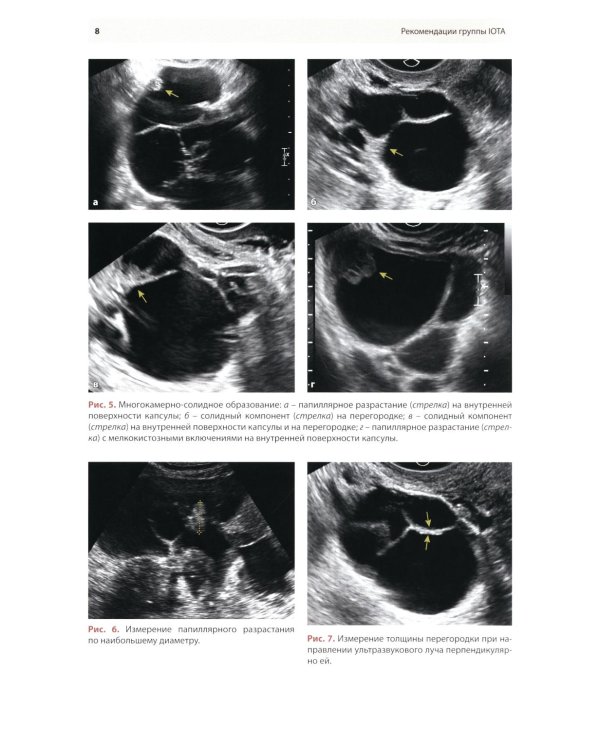

Методические рекомендации по стандартизации ультразвукового исследования с целью своевременной диагностики опухолевого процесса. Книга также включает вопросы дифференциальной диагностики физиологических изменений яичников, опухолевидных и опухолевых заболеваний и маршрутизации пациенток. Утверждено в качестве методических рекомендаций для проведения циклов первичной переподготовки врачей по ультразвуковой диагностике, тематического усовершенствования «Ультразвуковая диагностика в гинекологии», общего усовершенствования, ординаторов и аспирантов, проходящих обучение по направлению «Ультразвуковая диагностика, акушерство и гинекология».| Издательство | МЕДпресс-информ |